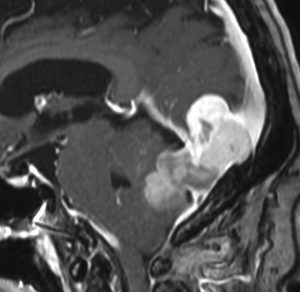

画像と病理所見1

右中頭蓋窩から側頭下窩に抜けた,三叉神経鞘腫と誤診しやすいSFTです。dense collagen fiber の中に,核内空胞を有する異型細胞が密に増殖しています。MIB-1染色が10%程度と高いSFTでGrade IIb SFTと分類されるものです。